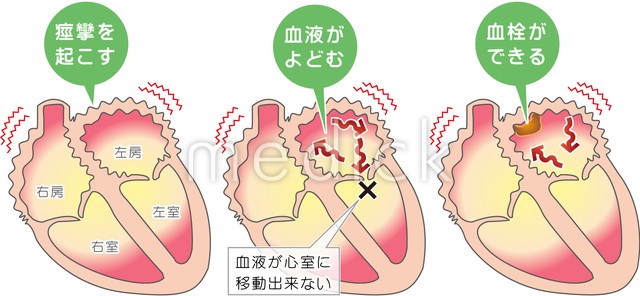

6.心房細動と血栓塞栓症心房細動について心臓・血管の話 - みやけ内科・循環器科。